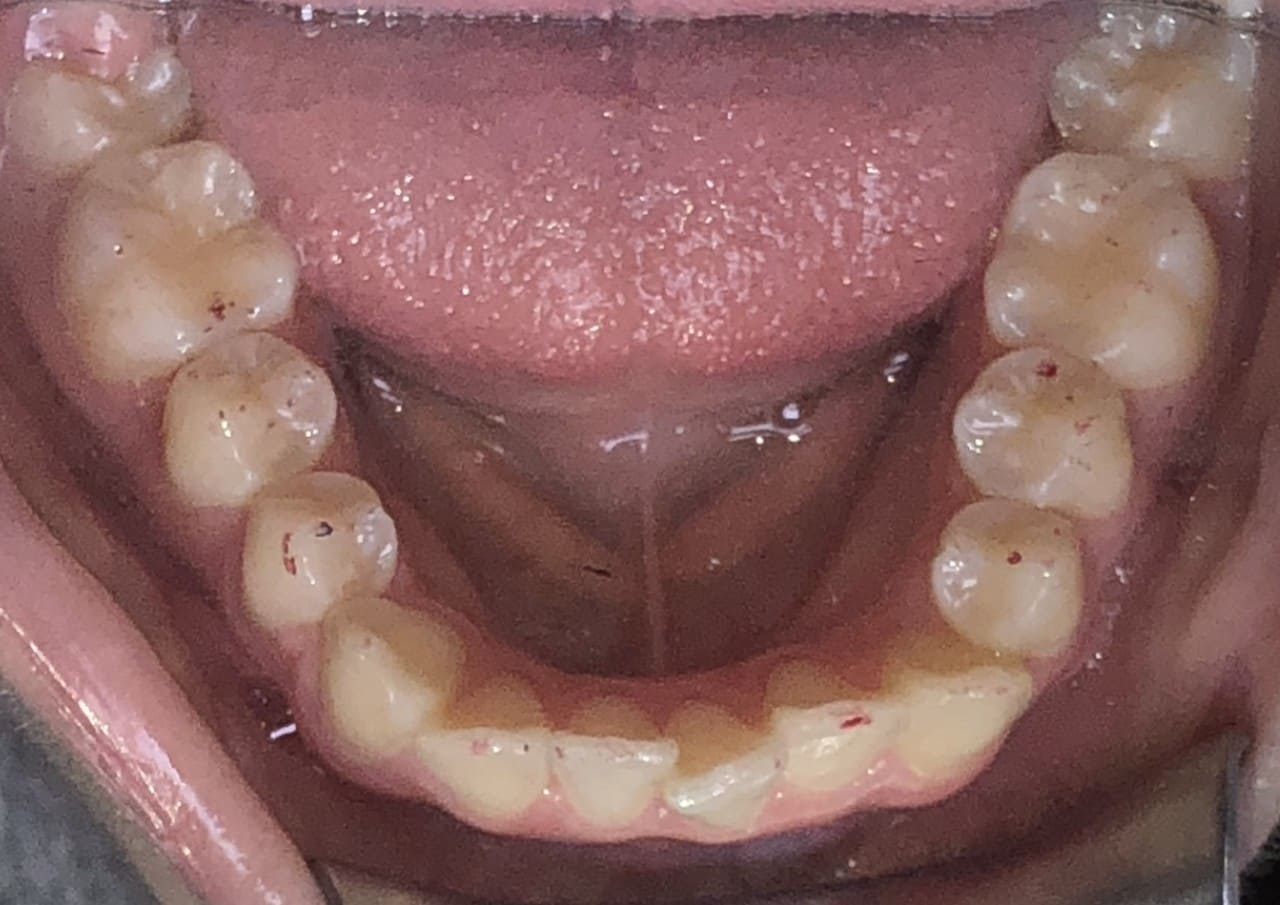

Initial